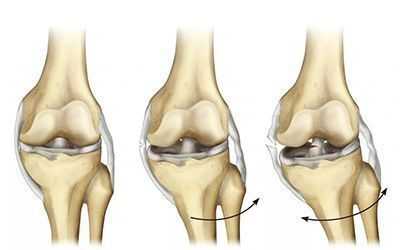

Зачастую при такой травме, помимо разрыва ПКС, повреждается внутренний мениск, а при сильном скручивании разрывается внутренняя боковая связка. Такое сочетание повреждений называют «несчастливой триадой» или «взрывом коленного сустава» [1] . При отклонении голени внутрь и кручении бедра наружу к травме ПКС может присоединиться разрыв наружного мениска.